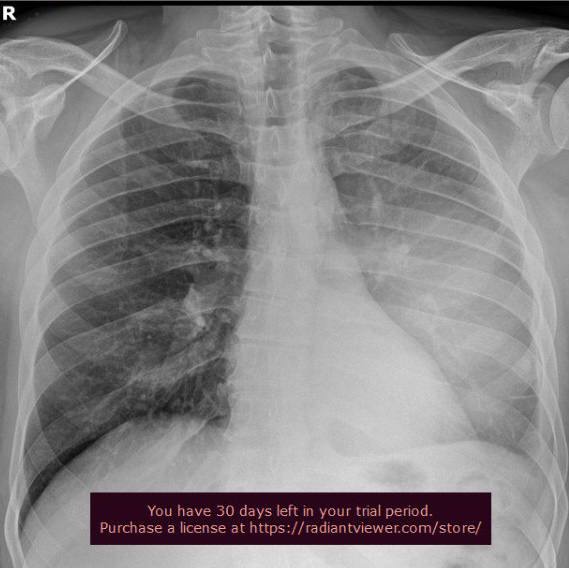

На рентгенограмі ОГК в прямій та боковій проекціях візуалізується рівномірне зниження повітряності у середньому та нижньому полі зліва, на бічній інтенсивне затемнення основою донизу в задніх та середньонижньому відділі ( від 4 ребра до заднього синуса). Легеневий малюнок незначно посилений. Корені легень структурні. Діафрагма без змін. Тінь серця та аорти в межах норми.